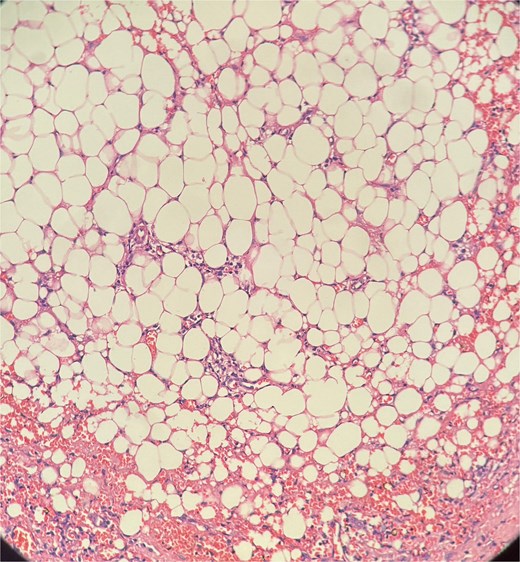

Picture depicting evidence of fat necrosis in the excised perianal tissue.

Sections show a dense inflammatory infiltrate within the subcutaneous adipose tissue, consistent with panniculitis. The infiltrate is composed of neutrophils, lymphocytes, plasma cells, and histiocytes.

Histopathological examination showed ghost-like adipocytes and foamy histiocytes.